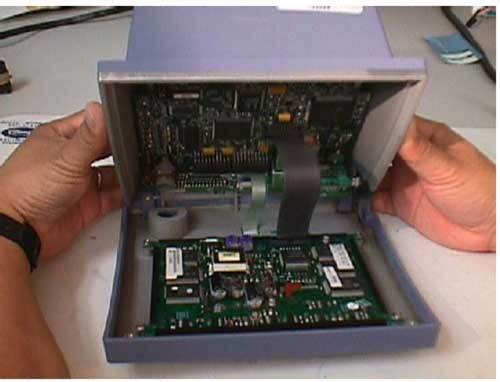

دستگاه Finapres: این دستگاه برای اندازه گیری فشار خون بصورت غیر تهاجمی و پیوسته مورد استفاده قرار میگیرد. این دستگاه بر خلاف فشار سنجهای معمولی بصورت لحظه به لحظه و با کمک تکنیک فوتوپلتیسموگرافی فشار خون بیمار را می سنجد. برای کاربردهایی مانند تست تیلت در موارد سنکوپ بیمار، ارزیابی سیستم عصبی اتوماتیک، بازیابی تغییرات همودینامیک در اتاق عمل یا سایر بخشهای بیمارستان، تعیین فشاررخون سیستول و دیاستول و …